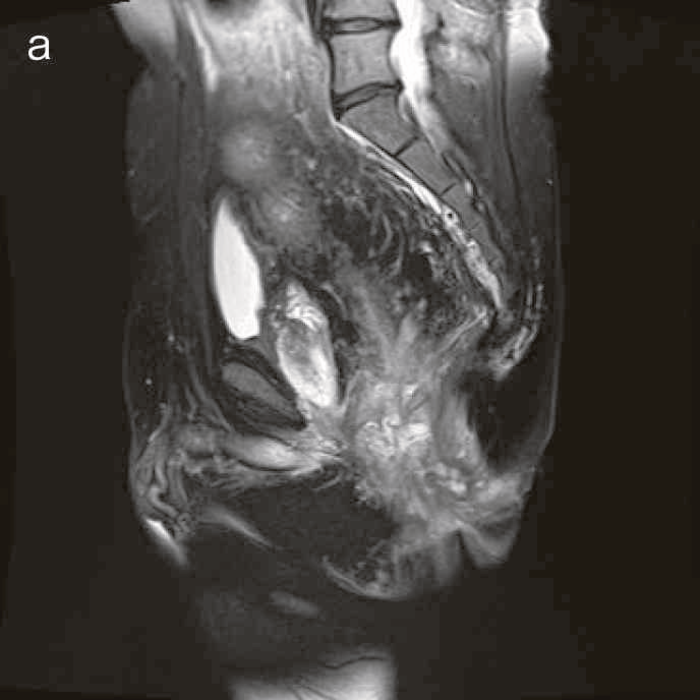

図41 腹部骨盤MRI

診断時のMRIでは直腸下部壁内から周囲にhigh intensity areaが拡がり,右側には痔瘻の瘻管を認めた。high intensity areaは前方で前立腺や陰茎海綿体付近まで広がっていた。

図38 骨盤部MRI

術前の骨盤部MRIでは右側の痔瘻瘻管と,左側の瘻管,周囲のリンパ節腫大を認めた。

明らかな癌を示す所見は不明であった。